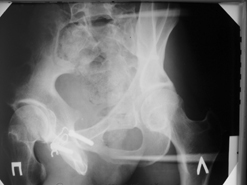

Диагноз : Сочетанная травма. ЗЧМТ. Перелом свода черепа. Ушиб головного мозга.Разрыв лонного и крестцово-подвздошного сочленений с нарушением целостности тазового кольца, с массивной забрюшинной гематомой и пропотеванием в брюшную полость. Перелом 10 ребра справа, осложненный гемопневмотораксом справа, правосторонней пневмонией на фоне ушиба правого легкого. Шок 3-4 ст. Больной поступил в отделение 07.03.2005г. в 16.00 в экстренном порядке через 30 минут после автодорожной травмы.Доставлен КСП. При поступлении состояние больного крайне тяжелое, явления травматического шока, А/Д-80/60 мм.рт. ст. ЧСС-120.В экстренном порядке поднят в операционную, интубирован, совместно с диагностическими мероприятиями лечение шока.При осмотре выявлены перелом 10 ребра справа, разрыв лонного и правого крестцово-подвздошного сочленений. Имеется линейный перелом теменной и височной костей слева с переходом на основание. Диагностическая лапароскопия 07.03.2005г. в 16.30-массивная забрюшинная гематома малого таза.Оставлена контрольная, дренажная трубка.Учитывая кровь в моче произведена цистография - данных за разрыв мочевого пузыря не найдено. Больной переведен в реанимационное отделение.За 08.03.2005г. из брюшной полости выделилось до 1500,0 мл, крови, часть крови реинфузирована. 08.03. в 06.30 наложен торокоцентез справа,удалено 100,0 мл. крови и 200,0 мл. воздуха .. Учитывая продолжающеееся кровотечение в брюшную полость из перелома костей таза, для исключения возможного разрыва внутренних органов 09.03.2005г. произведена Видеолапароскопия., на которой повреждения органов брюшной полости не выявлено.Одновременно произведен шов лонного сочленения проволокой и винтами, с одномоментным наложением стержневого аппарата на кости таза, с целью уменьшения кровотечения из разрывов тазовых сочленений, дренирование гематом. В последующем состояние больного оставалось тяжелым. 10.03.наложена нижняя трахеостома.Далее неоднократно производилась лечебно-диагностическая ФБС.С 10.03 выявлена правосторонняя плевропневмония. КТ головного мозга от 10.03-субарахноидальноекровоизлияние.Срединные структуры не смещены. КТ-контроль от 15.03-открытая моновентрикулярная гидроцефалия4 желудочка. Полисинусит. Постепенно состояние больного медленно прогрессировало к улучшению.С 24.03 переведен на самостоятельное дыхание, а 09.03 переведен в травматологическое отделение.Аппарат стержневой снят из-за перелома стержня (раскрутил больной самостоятельно).После госпитализации в наше отделение проведено дополнительное обследование Рентгекнография, КТ.Хотелось бы услышать Ваше мнение о дальнейшей тактике.-- С уважением, Leonid

Углядел билатеральное повреждение таза. Имеется вертикальная нестабильность со стороны перелома боковой массы крестца, ротационная с контрлатеральной стороны - чрезподвздошный разрыв кп сочленения. Разрыв лона, запирательные отверстия вроде целы.

DS. на сегодняшний день: Вертикальная двусторонняя нестабильная деформация таза, неправильно срастающийся перелом боковой массы крестца слева, срастающийся перелом крыла правой подвздошной кости, застарелый частичный разрыв правого кп сочленения, застарелый разрыв лонного сочленения.

План жизни - оперативное лечение. ЧКО таза (кольцевая опора), последовательная фиксация задних отделов с низведением перелома крестца, синтез лона пластинами, илиосакральное блокирование.

Следует заметить, что подобное привинчивание проволокой лонных костей редко приносит удовлетворение и то только при ротационно-нестабильных повреждениях от бовового сжатия без "ручки корзины". Разрушение заднего комплекса делает неэффективным любую фиксацию передних отделов. Надо обезательно хватать задние отделы.